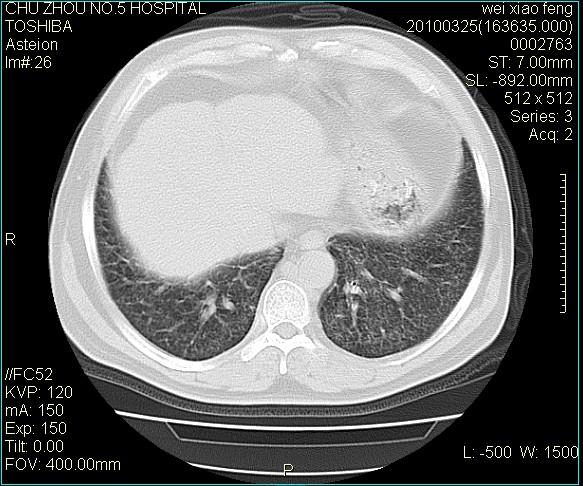

男,60岁,反复咳、痰、喘3月,加重3天。

追问病史:此病人无职业病接触史,无发热、盗汗,咳白痰,曾经有过咯血。

考虑双肺血型潘散肺结核/

急性血型潘散肺结核。

双肺间质纤维化,双肺血型潘散肺结核。

肺泡癌不除外

右肺中叶结节影为原发灶,考虑右肺中叶周围型肺癌并淋巴道转移